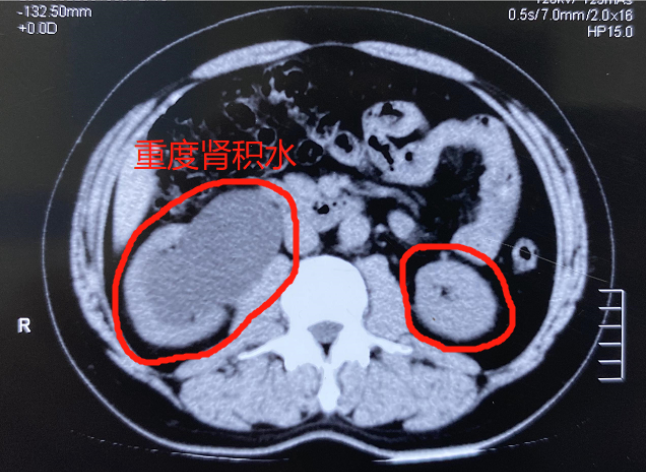

疼痛位置多为腰部,可出现持续性钝痛、隐痛等,劳累后症状加重,经常会伴随血尿。部分患者则因为结石位置问题,可长期无明显症状,但在检查时,可能会出现肾积水等现象。